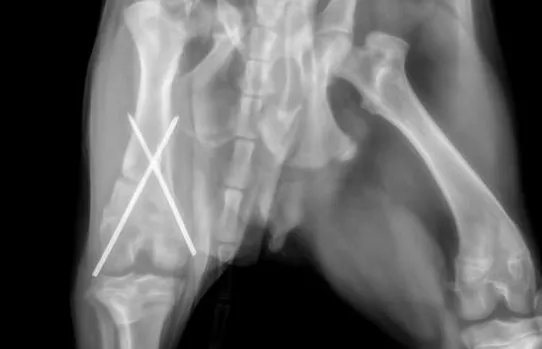

- Fracture repair (Plating, plate/rod, cross pin, compressive screw, etc.)

Fracture Repair Services

At Caring Hands, while our doctors are general surgeons and not board-certified orthopedists/surgeons, they are orthopedically trained by the AO organization which is a prestigious international orthopedic foundation that focuses on orthopedic care in both human and veterinary patients. We offer robust fracture repair options through the use of high-quality plating systems, rods, pins, wires, and screws. If you're worried that your furry loved one has broken his/her leg, our doctors will start by taking x-rays and then will develop a plan using special fracture planning software before operating. We will provide you an honest estimate, and provide you with several options of how to carry that plan out which in limited situations may include referral to specialists if its a case we don't feel comfortable operating on. We do take referrals from other hospitals that don't operate on bones! Give us a call and we will happy to serve you in anyway we can.

Caring Hands is proud to use very high quality human-quality orthopedic plating equipment (Movora/VOI) and orthopedic drills (Stryker)